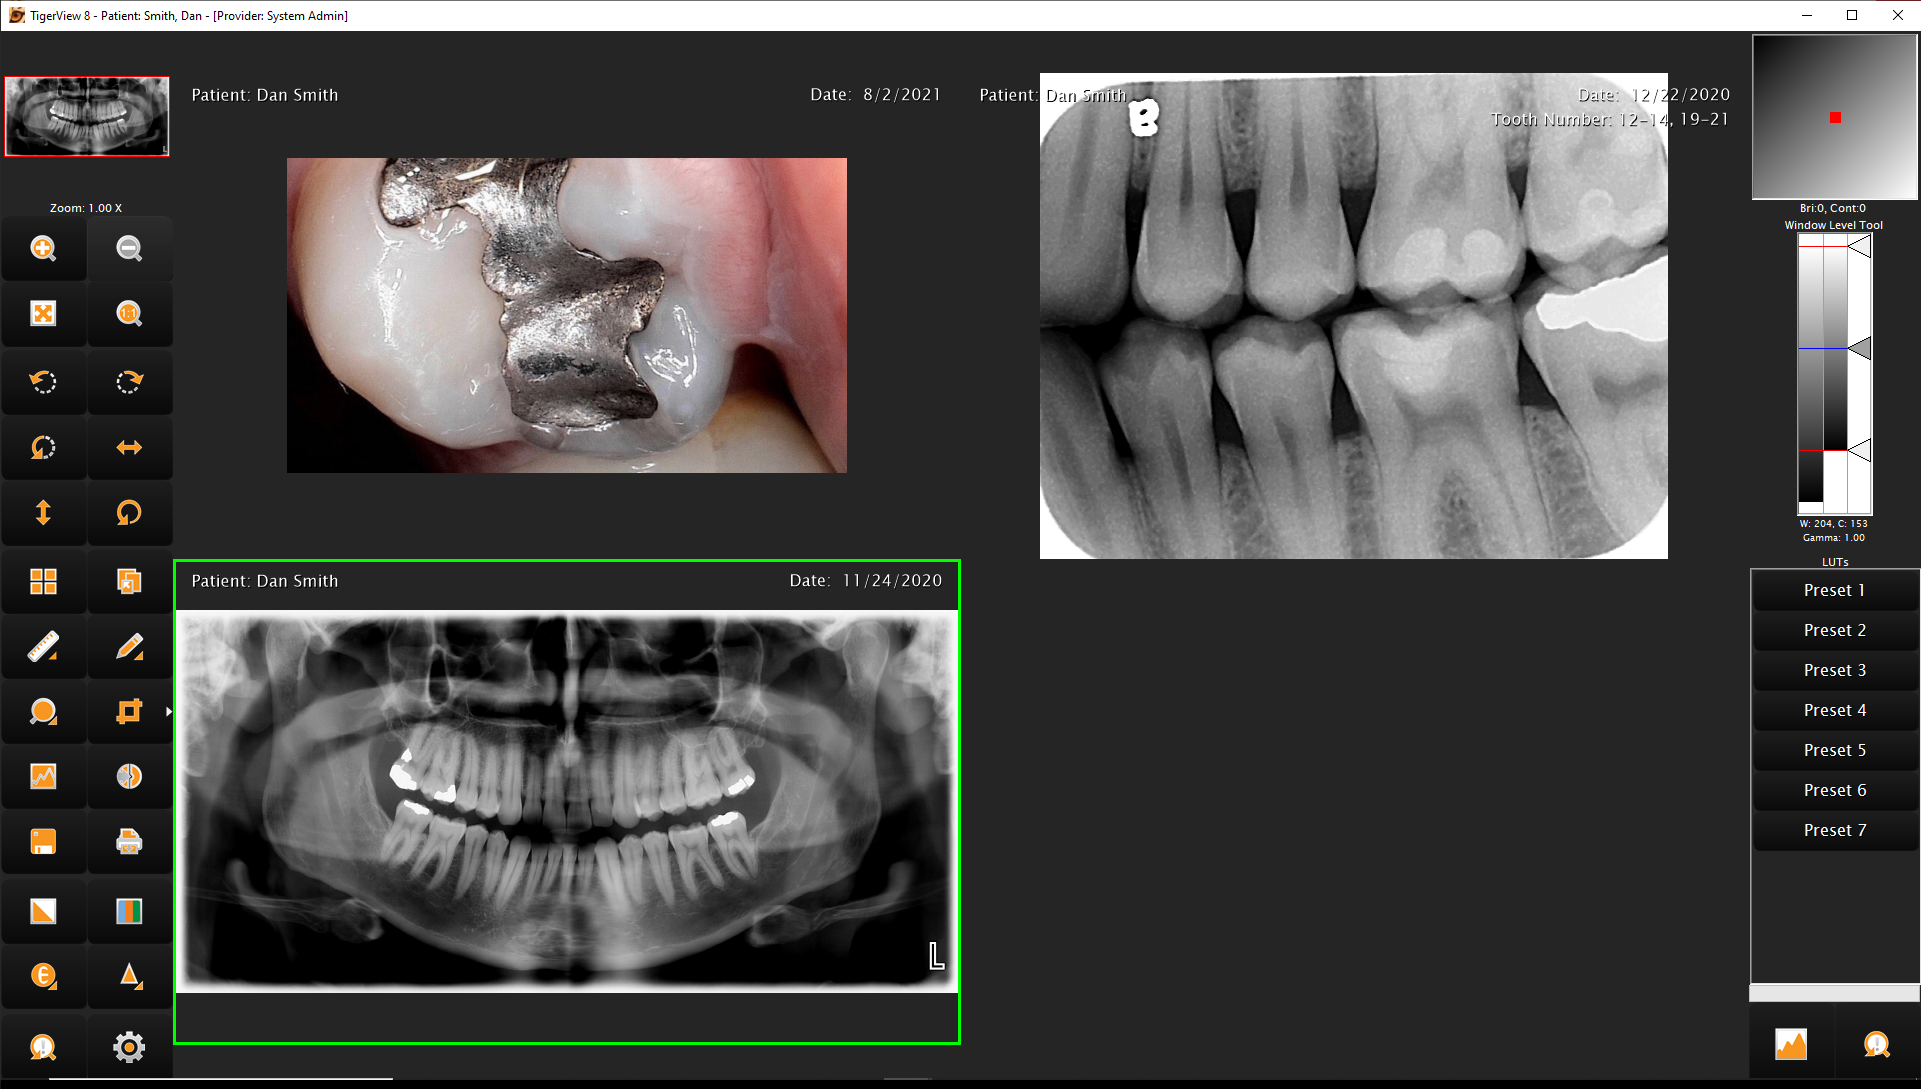

The TigerView Imaging Base Package is the foundation of a modern dental imaging workflow. Designed specifically for dental practices, TigerView allows you to capture, store, view, and share all diagnostic images — including digital X-rays, panoramic images, intraoral camera photos, and scanned film — from a single, unified platform.

Built with a user-friendly interface and DICOM 3.0 compliance, TigerView supports a wide range of imaging hardware from multiple manufacturers. This flexibility allows your practice to choose the equipment that fits your needs without being locked into proprietary systems. All images are stored in one database, making it easy for your team to access, compare, and present images across multiple exam rooms.